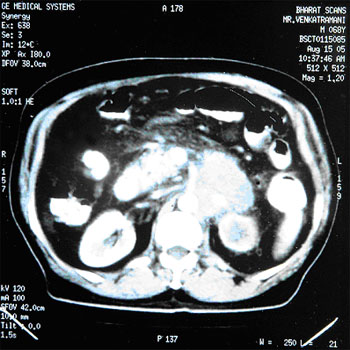

• Cured cancer using Herbal Oncology and proved with PET scans